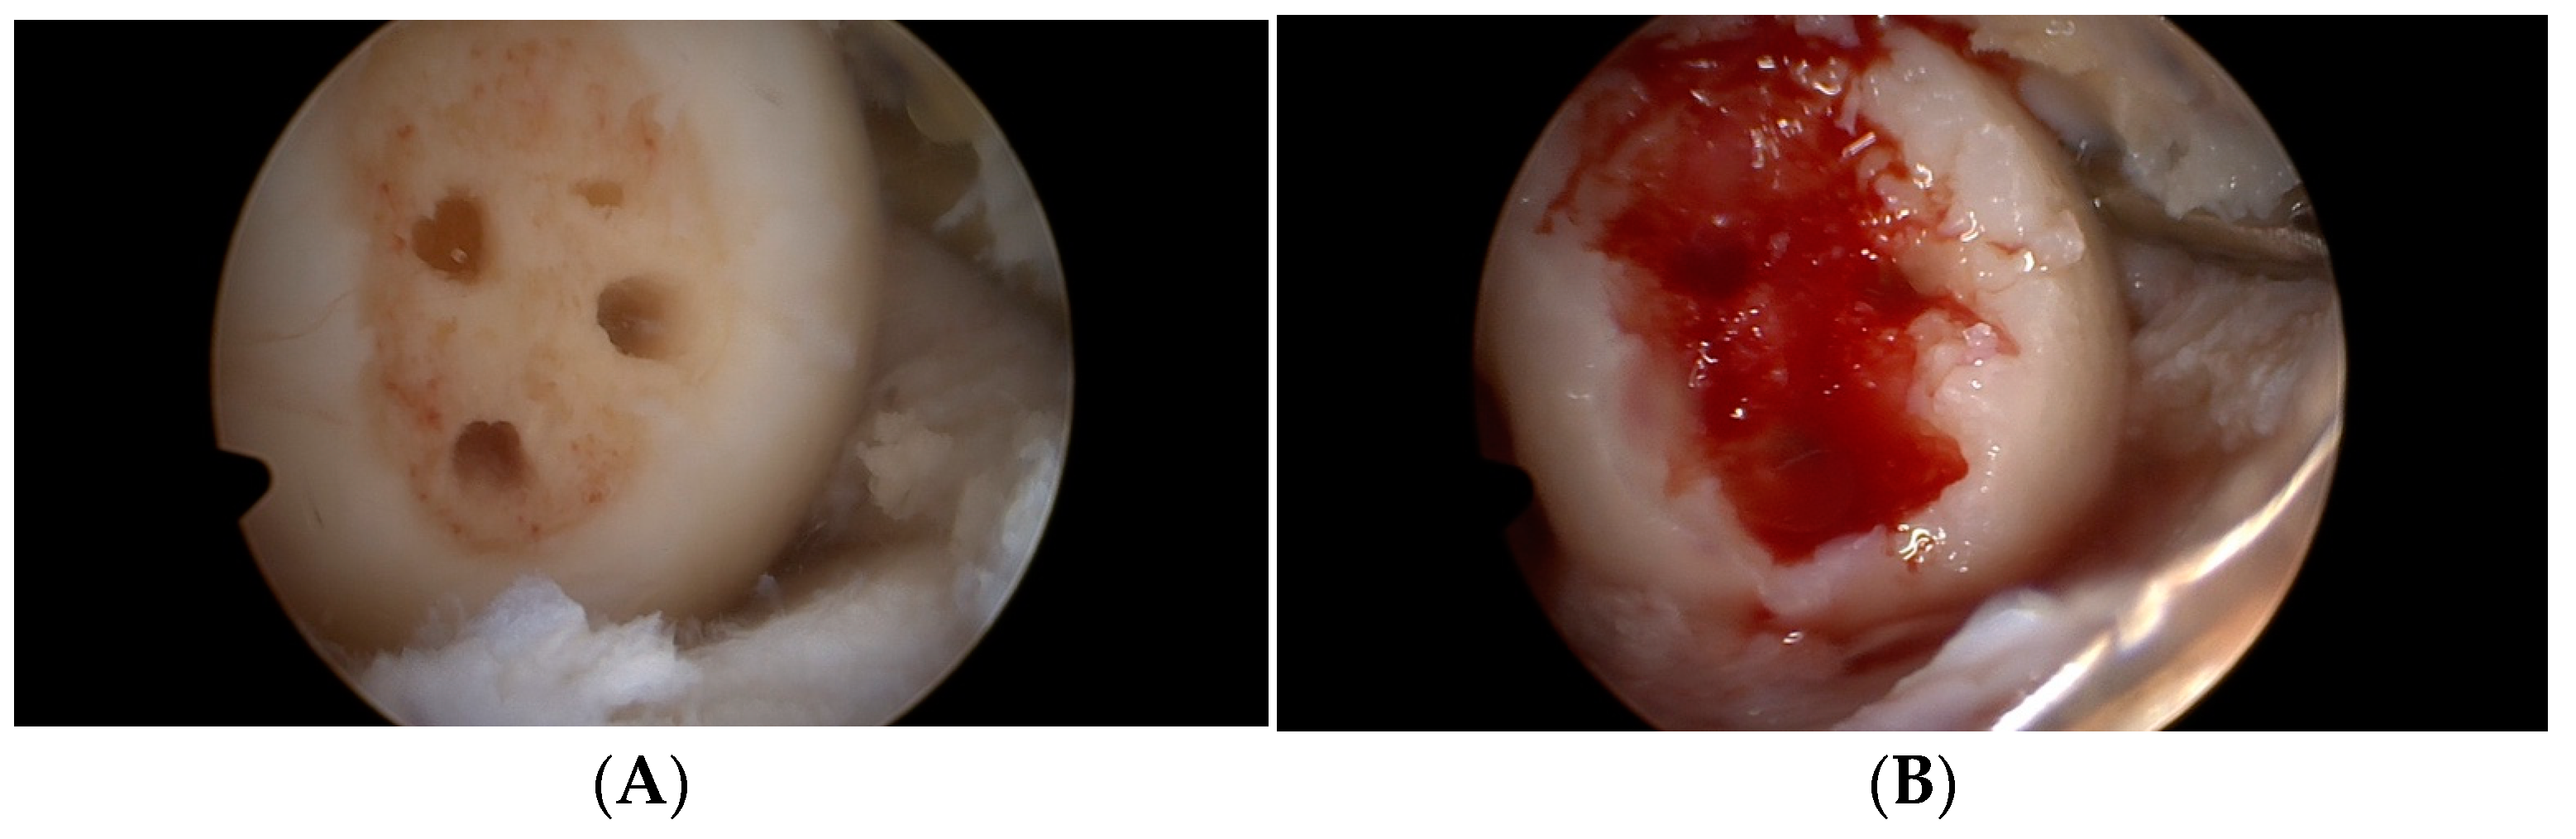

2.2. Operation Procedure